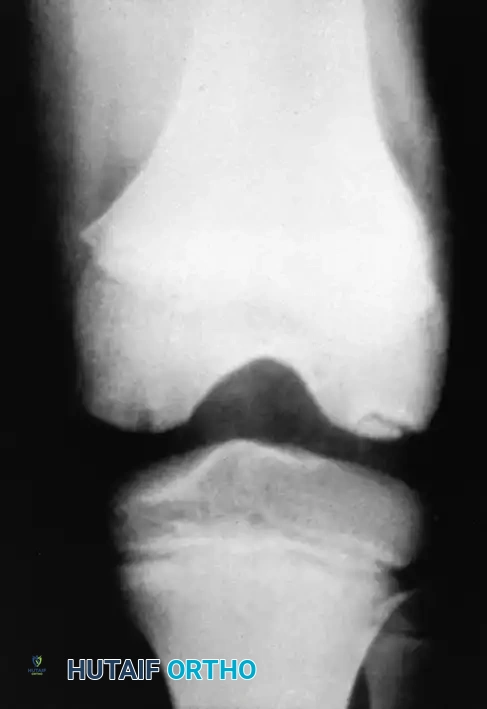

Osteochondritis dissecans (OCD) of the ankle primarily affects the talar dome. The natural history of this lesion in children with open physes is highly favorable compared to adult populations.

Natural History and Imaging

Bauer et al., in a long-term follow-up study (≥ 20 years) of 30 children with ankle osteochondritis, found that only one patient developed severe osteoarthritis. The vast majority experienced complete healing with only minor residual radiographic changes. This is in stark contrast to osteochondritis of the knee, where secondary osteoarthritis is a frequent complication.

Radiographic and MRI evaluation of osteochondral lesions of the talar dome, demonstrating subchondral separation and surrounding edema.